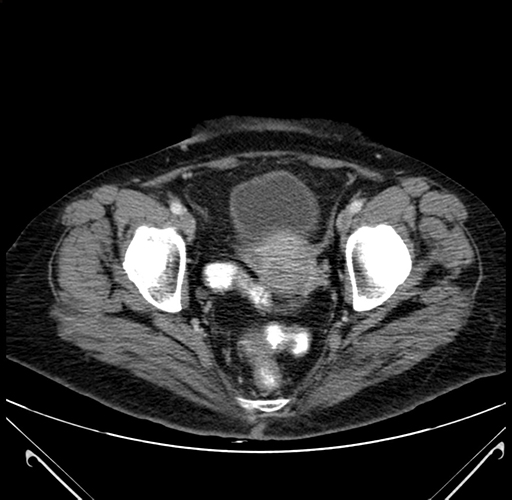

Pre-Chemo: Axial Venous

Axial Venous